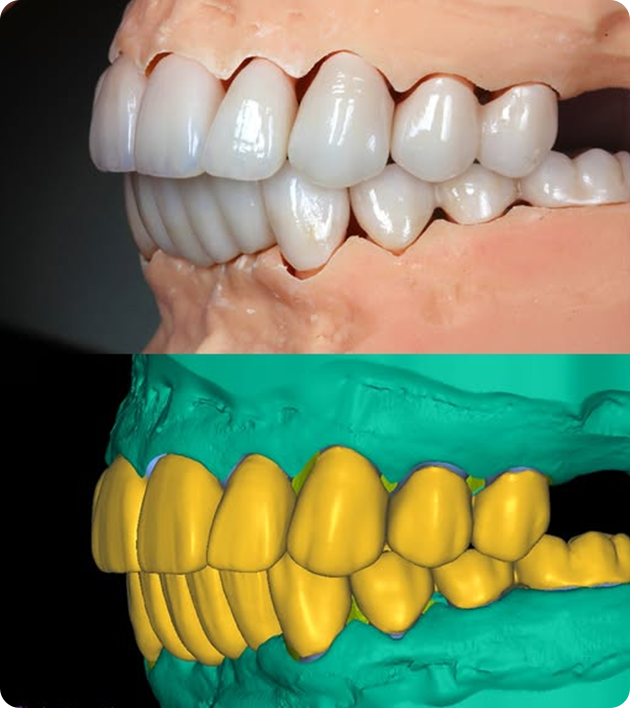

Digital Mock-up

With Digital Mock-Ups, you can see the future of your smile — in full 3D — before any procedure takes place.

What Is a Digital Mock-Up?

Visualize First. Treat Next.

Digital mock-ups use advanced imaging and design software to create a virtual simulation of your post-treatment smile. Whether it's veneers, aligners, or implants, you'll get to see your results before committing.

How It Works

• Scan & Capture:

We begin with digital scans of your teeth and facial photos to capture every detail.

• Design & Plan:

Using smile design software, we customize your ideal smile based on your facial symmetry and personal preferences.

• Virtual Smile Preview:

See your transformed smile digitally — from multiple angles, even in motion.

• 3D Printed Trial (Optional):

Test-drive your new look with a temporary restoration created from the mock-up.